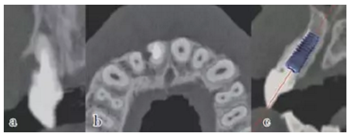

患牙21因根管治療超充,導(dǎo)致根尖周炎,唇側(cè)齲壞并出現(xiàn)瘺管。擬采用即刻種植修復(fù)。術(shù)前拍攝CBCT并做種植方案規(guī)劃,從方案上可知唇側(cè)及遠中側(cè)骨缺損較為嚴(yán)重,需要同期進行引導(dǎo)骨再生術(shù)(GBR)。

圖9 種植方案規(guī)劃:a.近遠中方向的截面圖,唇側(cè)需要GBR;b.軸向截面圖;c. 模擬植入4.0×13 mm 的種植體